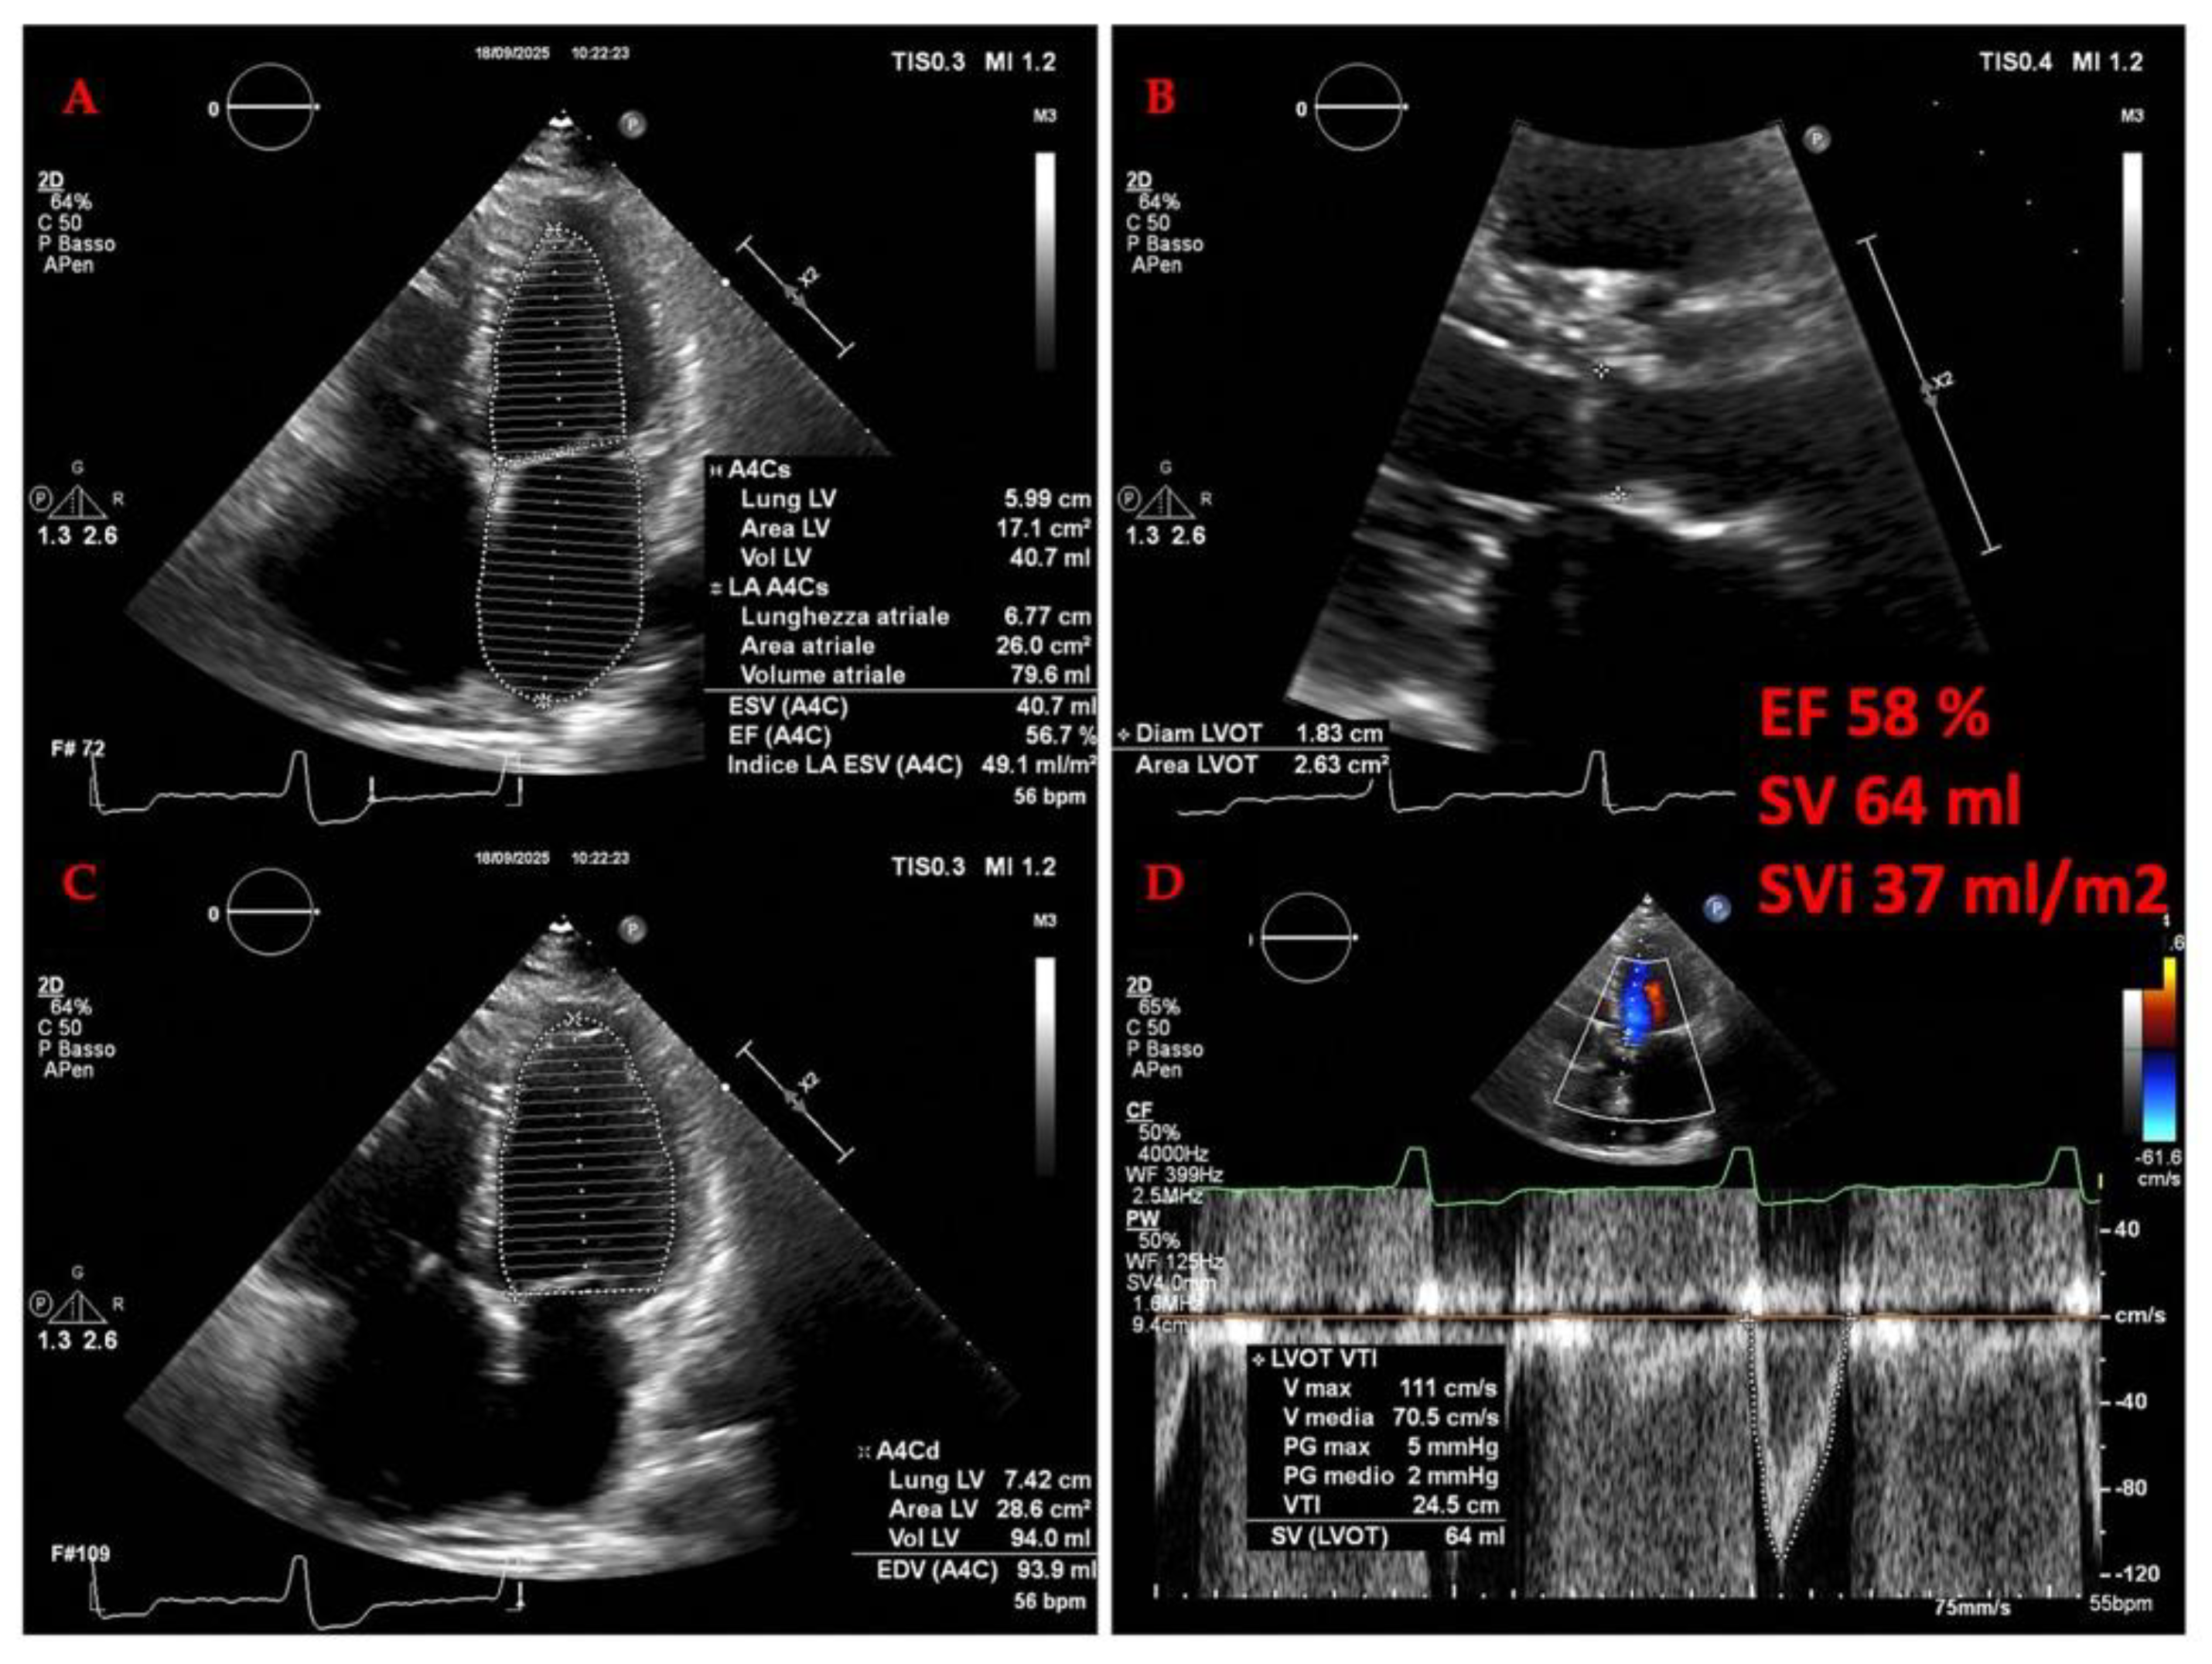

4.2. Cardiac Evaluation: Echocardiography

4.2.1. The Evolving Role of Echocardiography OF LEFT HEART in Heart Failure